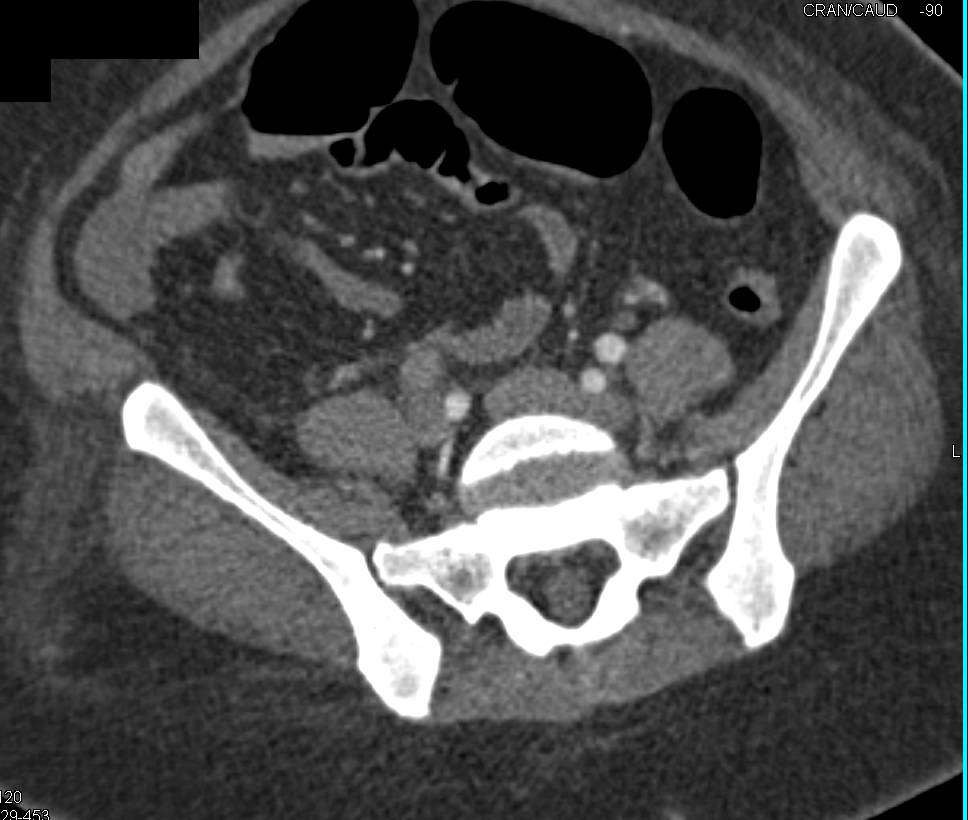

CTA with Occluded Superficial Femoral Artery (SFA)-Popliteal Artery Bypass Graft